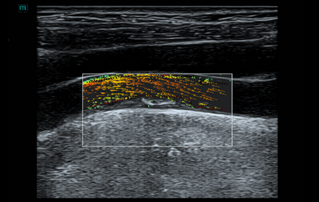

![carotid-plaque-conventional-innovation-technique.thumb.319.319 Ultrasound Journal 40 - Carotid Plaque: Conventional and Innovation Technique]() Ultrasound Journal 40 - Carotid Plaque: Conventional and Innovation TechniqueConventional Doppler underestimates irregular carotid stenosis and misses IPN. See how Resona A20ŌĆÖs area-based quantification and V Flow WSS/Tur parameters solve these limitations.Ultrasound Cases | Ultrasound | Smart applications | Cardiology 2026-01-09

Ultrasound Journal 40 - Carotid Plaque: Conventional and Innovation TechniqueConventional Doppler underestimates irregular carotid stenosis and misses IPN. See how Resona A20ŌĆÖs area-based quantification and V Flow WSS/Tur parameters solve these limitations.Ultrasound Cases | Ultrasound | Smart applications | Cardiology 2026-01-09 -